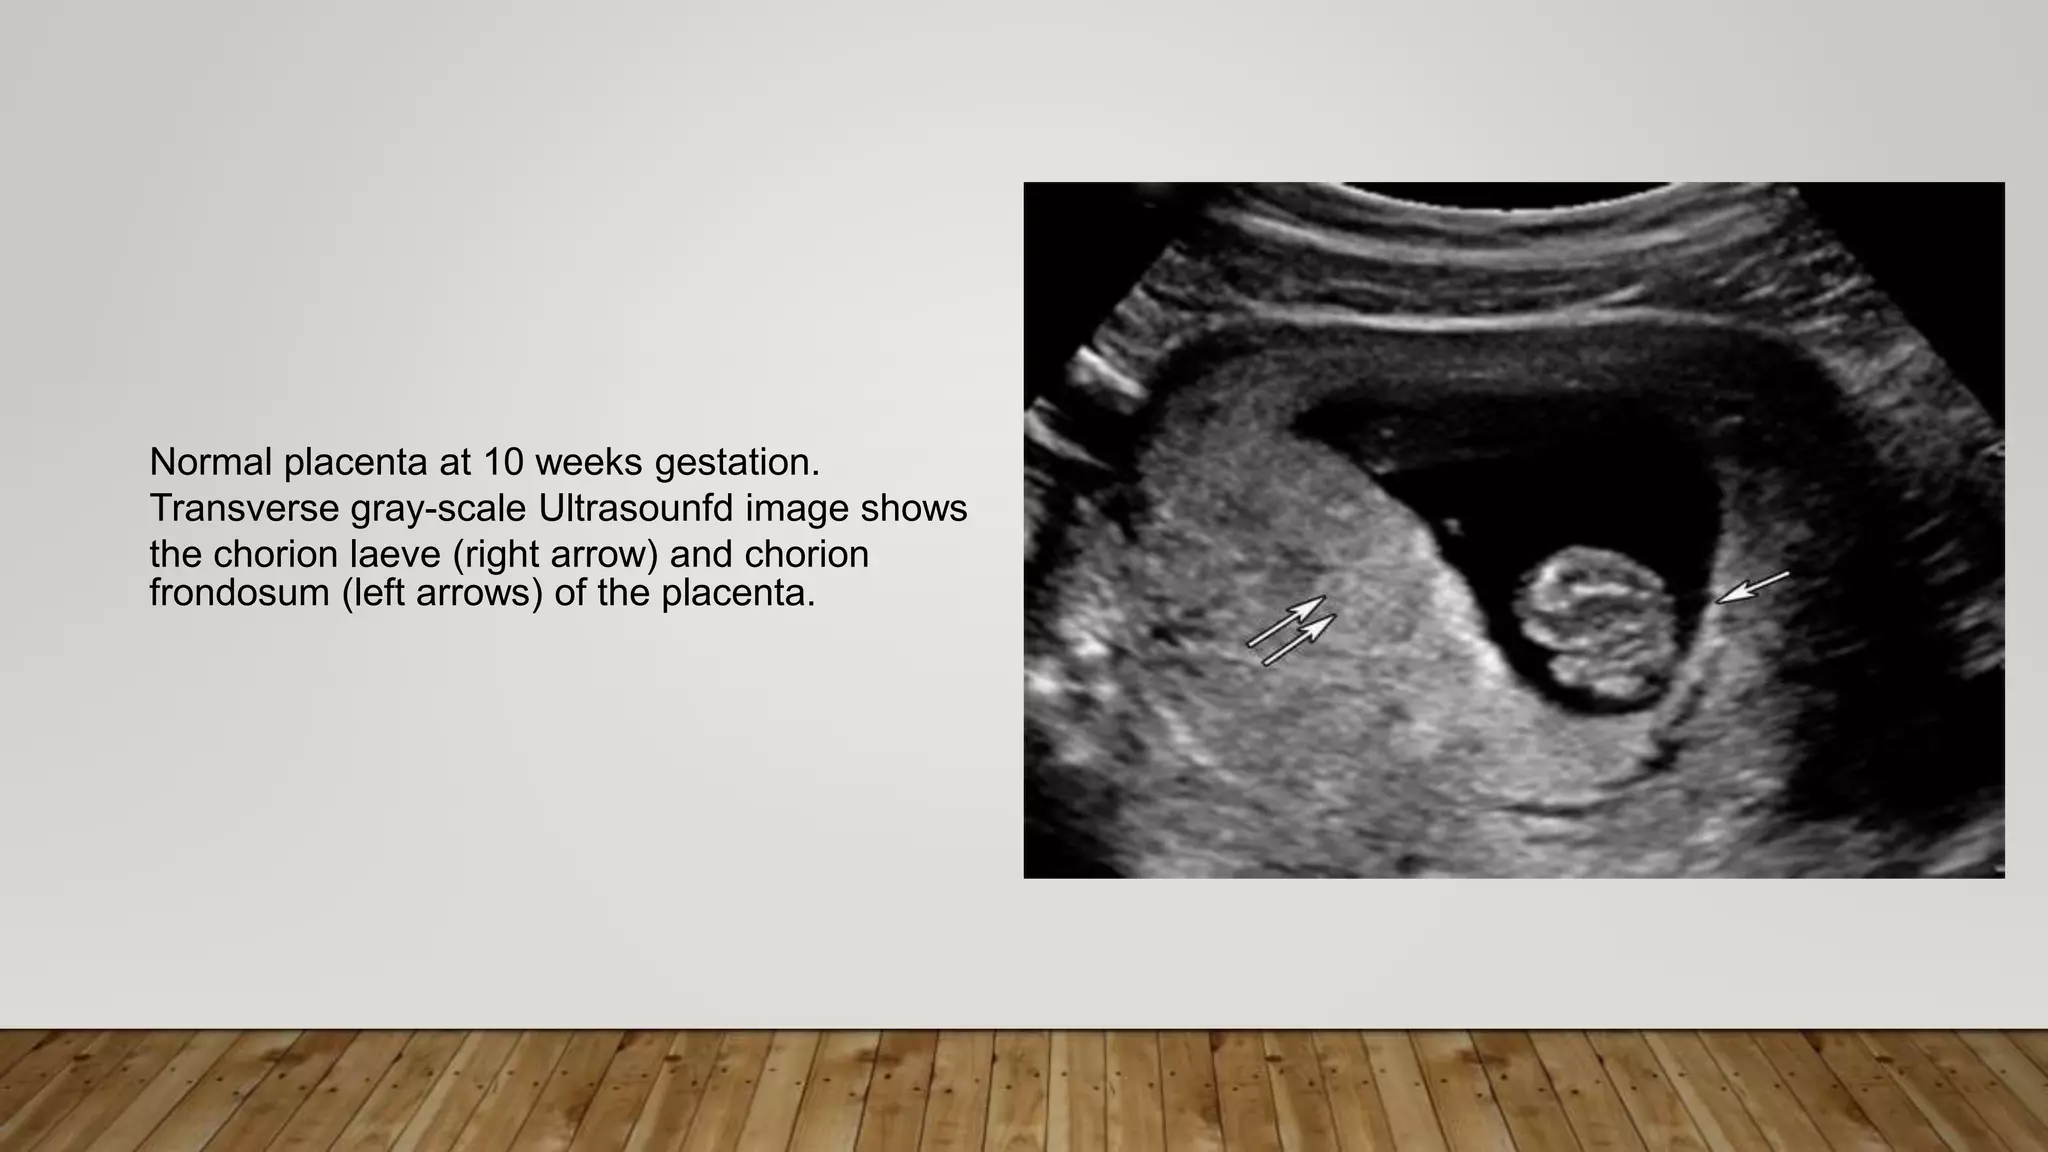

Normal placenta at 10 weeks gestation.

Transverse gray-scale Ultrasounfd image shows

the chorion laeve (right arrow) and chorion

frondosum (left arrows) of the placenta.